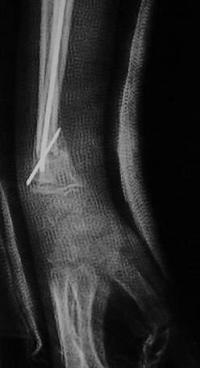

Métaphyse poignet -1 Radio initiale Profil

Radio initiale : bascule postérieure + chevauchement